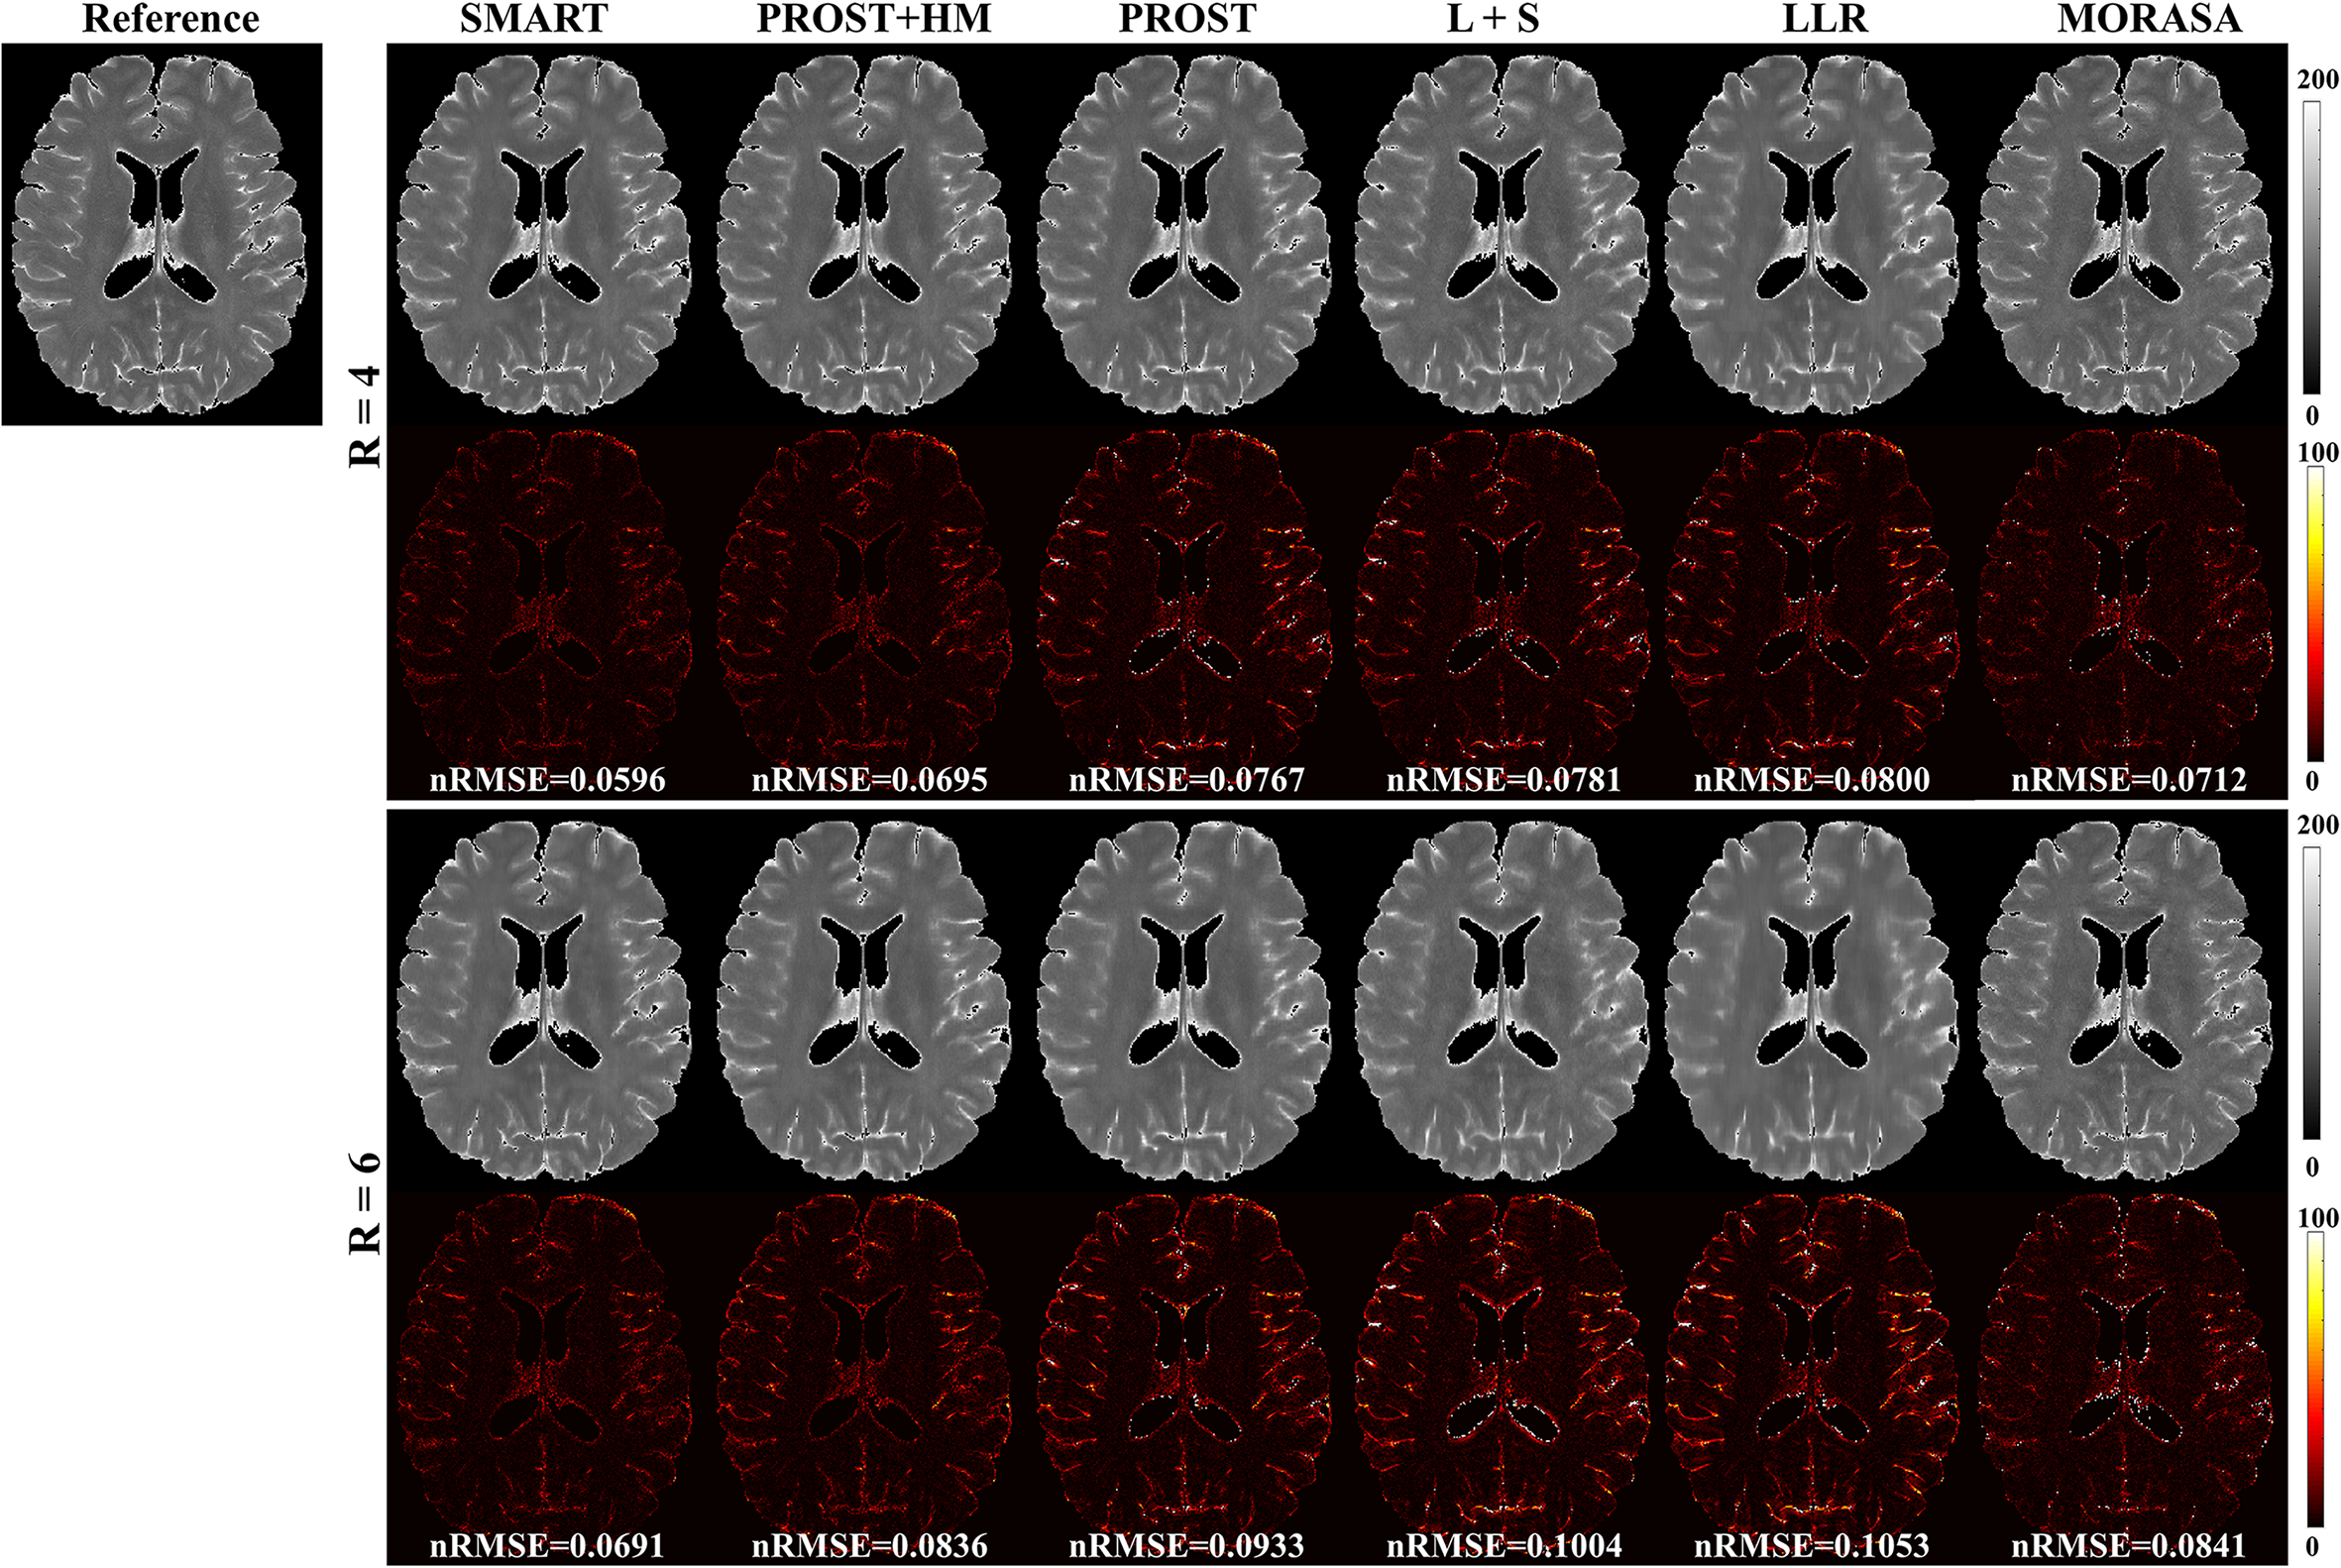

The -weighted images (at TSL = 1 ms) from one volunteer reconstructed using the SMART, PROST+HM, PROST, L+S, LLR, and MORASA methods are shown in Fig. 3. Difference images between the reconstructed and reference images are displayed under the reconstructions, and the nRMSE values are placed below the difference images. Table 1 lists the average HFEN, SSIM, and PSNR values for all reconstructed -weighted images at different TSLs. The estimated maps from the reconstructed and difference images are shown in Fig. 4.

4.2 Retrospective 2D Reconstruction

4.2.1 Low acceleration with 4-Fold and 6-Fold

| Metrics | SMART | PROST+HM | PROST | L+S | LLR | MORASA | |

|---|---|---|---|---|---|---|---|

| 4 | HFEN | 0.1858 | 0.2232 | 0.2359 | 0.2453 | 0.2645 | 0.2017 |

| SSIM | 0.9805 | 0.9762 | 0.9761 | 0.9737 | 0.9731 | 0.9780 | |

| PSNR | 43.2262 | 41.5372 | 41.1570 | 40.4791 | 39.8966 | 42.6131 | |

| 6 | HFEN | 0.2224 | 0.2671 | 0.2727 | 0.2897 | 0.3170 | 0.2553 |

| SSIM | 0.9761 | 0.9701 | 0.9704 | 0.9670 | 0.9641 | 0.9715 | |

| PSNR | 42.0636 | 40.0560 | 40.1768 | 39.6337 | 39.0524 | 41.0307 |